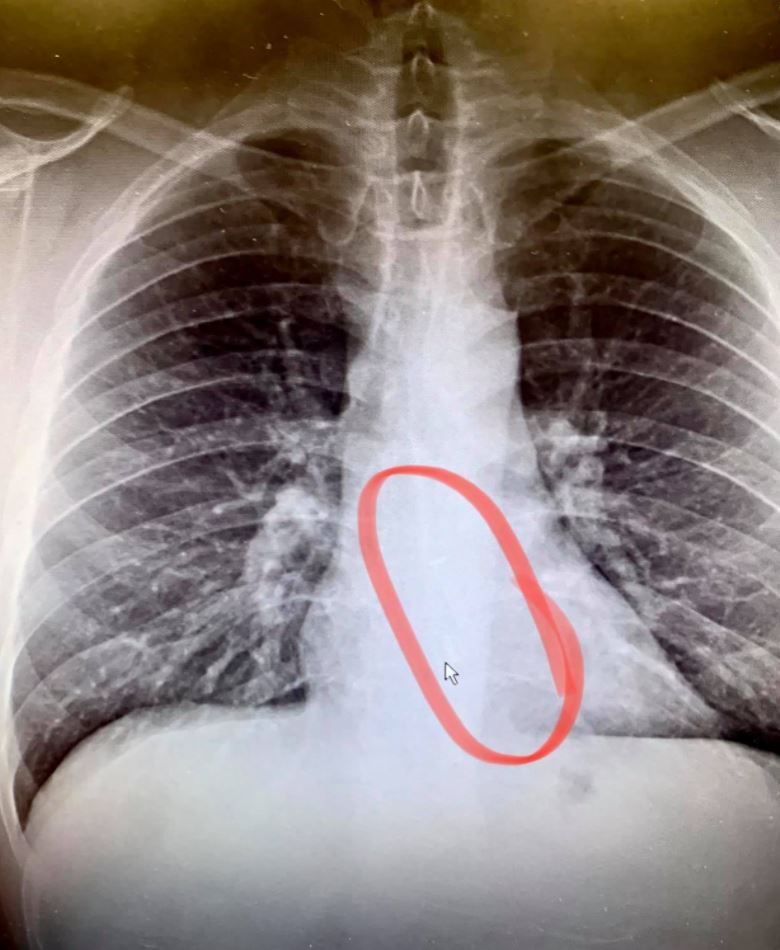

At the hospital, doctors found the AirPods in Gauthier’s esophagus. Furthermore, they performed emergency endoscopy and extracted AirPods from the windpipe. This incident is a reminder that sleeping with AirPods can be a safety hazard. The physician said Gauthier was lucky to be breathing.